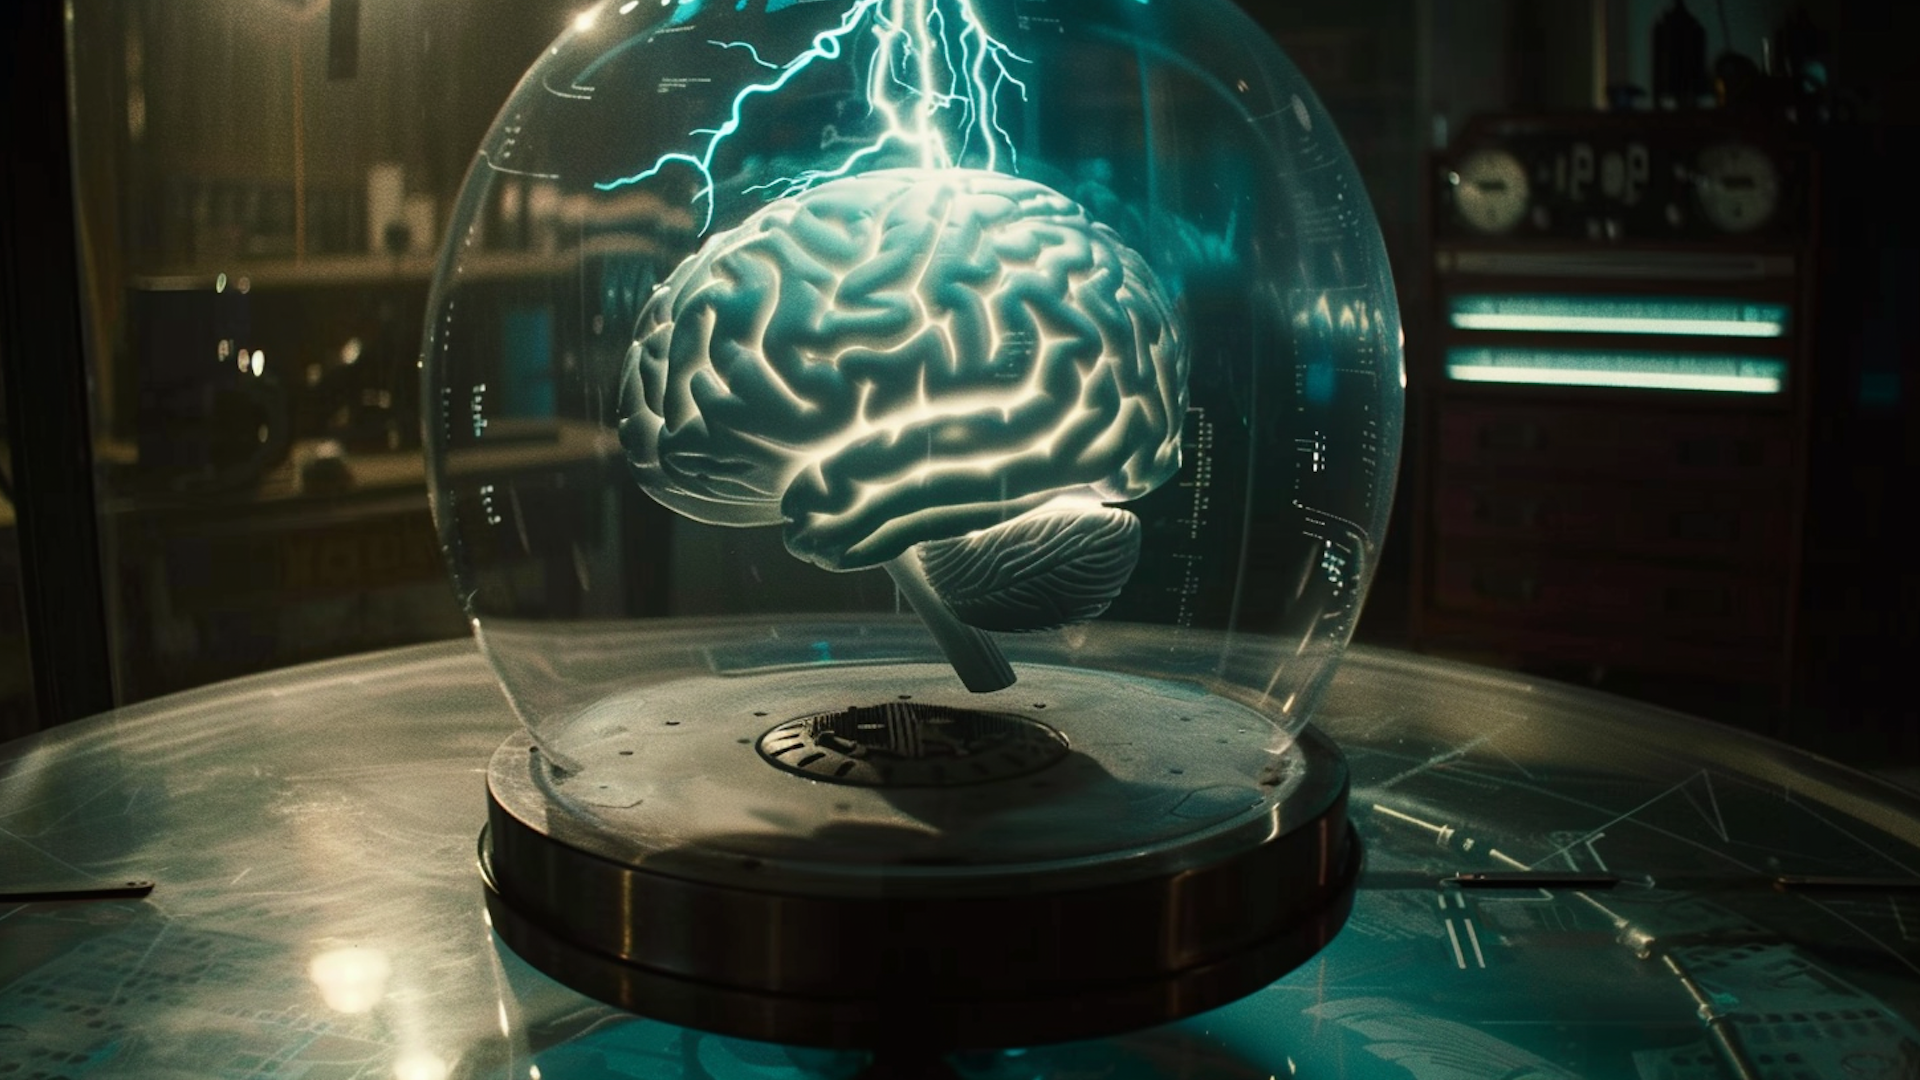

7. 脑部电子活动的3D显示:

2014年,与 STM Holography 和 Cerebral Diagnostics 合作,实验室开发了在睡眠期间捕捉和显示大脑电子活动的3D视图技术。

PHASE 实验室的 Michael Page 教授团队专注于利用全息图技术可视化方式,向公众和医务人员展示大脑在睡眠过程中所经历的复杂过程,」佩奇教授解释道。这种前沿技术潜力巨大,尤其在医学成像和教学领域。

2014 年,STM Holography and Cerebral Diagnostics 与 PHASE Lab 合作开发技术,以捕捉和显示睡眠期间大脑电子活动的 3D 视图。 「我们的研究重点是以商业标准 3D 格式创建大脑模型,然后将其整合到标准化全息图列印格式中,」佩奇说。 “Cerebral Diagnostics 希望能够将动画视频全息图通过FTP 传输到他们的服务局。” PHASE ab 取得了Cerebral Diagnostics 创办人兼执行长Mark Doidge 博士记录的资料集,并努力将其准确地转化为PHASE Lab 和STM Holography 商业服务局的全像印表机的「相机就绪艺术品」。 Page 表示,“这些全像图不仅以 3D 形式表示数据,还传递大脑电活动随时间变化的数据变化。”佩奇说,这项研究「领先于时代」。

脑电活动全息图|图片由 PHASE 实验室提供

- 大脑电子活动捕捉与显示:2014 年与 STM Holography and Cerebral Diagnostics 合作,研究在睡眠期间大脑电子活动的 3D 视图捕捉与显示技术。

实验室的目标是探索大脑活动如何与梦境和其他夜间过程相关联,最终创造出一种可以将脑电活动可视化的3D全息图。」佩奇解释道。这项合作不仅展示了全息技术在医学领域的潜力,还揭示了大脑研究新的可能性。